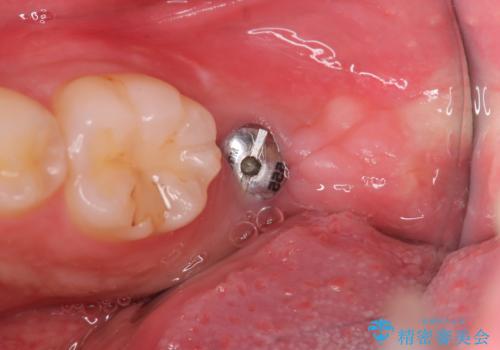

当院では、痛みの少ないインプラント治療を行っております。

実際に治療を受けられた多くの患者様からは、「腫れもなく、痛み止めをまったく使用しなかった、もしくは1〜3錠程度で済んだ」といったお声を頂いております。

インプラントの上部構造(被せ物)には「スクリュータイプ」と「セメントタイプ」の2種類がありますが、セメントタイプは残留セメントが原因となり、インプラント周囲炎を引き起こす可能性があります。

そのため、当院では基本的に清掃性やメンテナンス性に優れたスクリュータイプを採用しております。